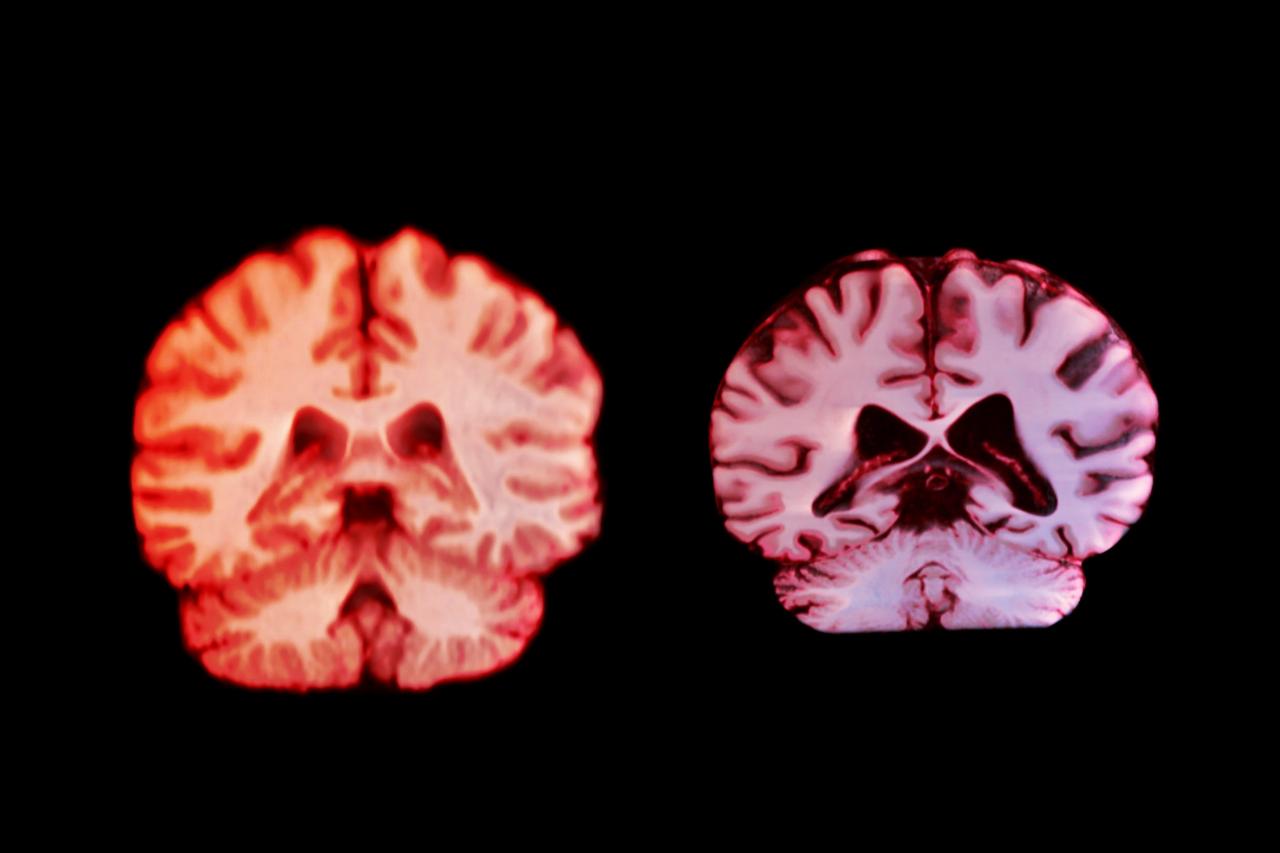

Nők és az Alzheimer – miért gyakoribb mégis?

Ennek ellenére az Alzheimer-kór esetében a nők vannak nagyobb veszélyben: majdnem kétszer annyi nő szenved ebben a betegségben, mint férfi. Ez meglepő lehet, hiszen ha a férfiaknál gyorsabb az agyzsugorodás, logikusnak tűnne, hogy inkább ők legyenek az érintettek. A kutatás azonban kimutatta, hogy épp ellenkezőleg: az Alzheimer-kór szempontjából kulcsfontosságú agyterületeken, például a memória működéséhez elengedhetetlen hippokampuszban, nem a nőknél gyorsabb az állapotromlás. Így a női túlsúly nem magyarázható csupán az öregedés agyra gyakorolt eltérő hatásaival.